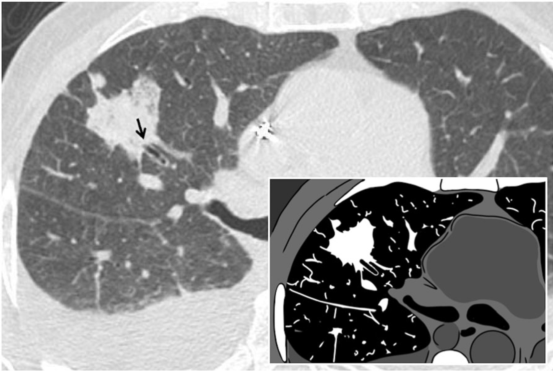

cheerios征是轴位断层图像中描述的一种征象,它是由一个含有小中心气腔的肺结节组成,由畅通的支气管供应气体 (图5)。它是由未闭塞的支气管分支周围的细胞增殖产生,可能为恶性或非恶性。1993年Reed和O'Neil[21]描述了次征象,指的是低级别肺腺癌。组织学上,可以复制cheerios征的肿瘤有原位腺癌、微浸润性腺癌、以鳞屑成分为主的浸润性腺癌或浸润性粘液腺癌。1997年Lee等将此征象与出现肺腺癌伴鳞屑型的结节性病变联系起来 [22]。它也可能与朗格汉斯X组织细胞增生症或脑膜上皮肺结节相关 [23]。空洞性结节可以区别出现cheerios 征的结节,因其坏死区域是由于坏死现象引起,而不是由于气道周围组织的增生。

图5. Cheerios 征。cheerios征是由于支气管分支周围的细胞增生所致 (白色箭),可见于郎格罕细胞组织细胞增生症或肺腺癌患者。此征象与著名的早餐麦片外观非常相似-似嵌入图形中显示的外观。